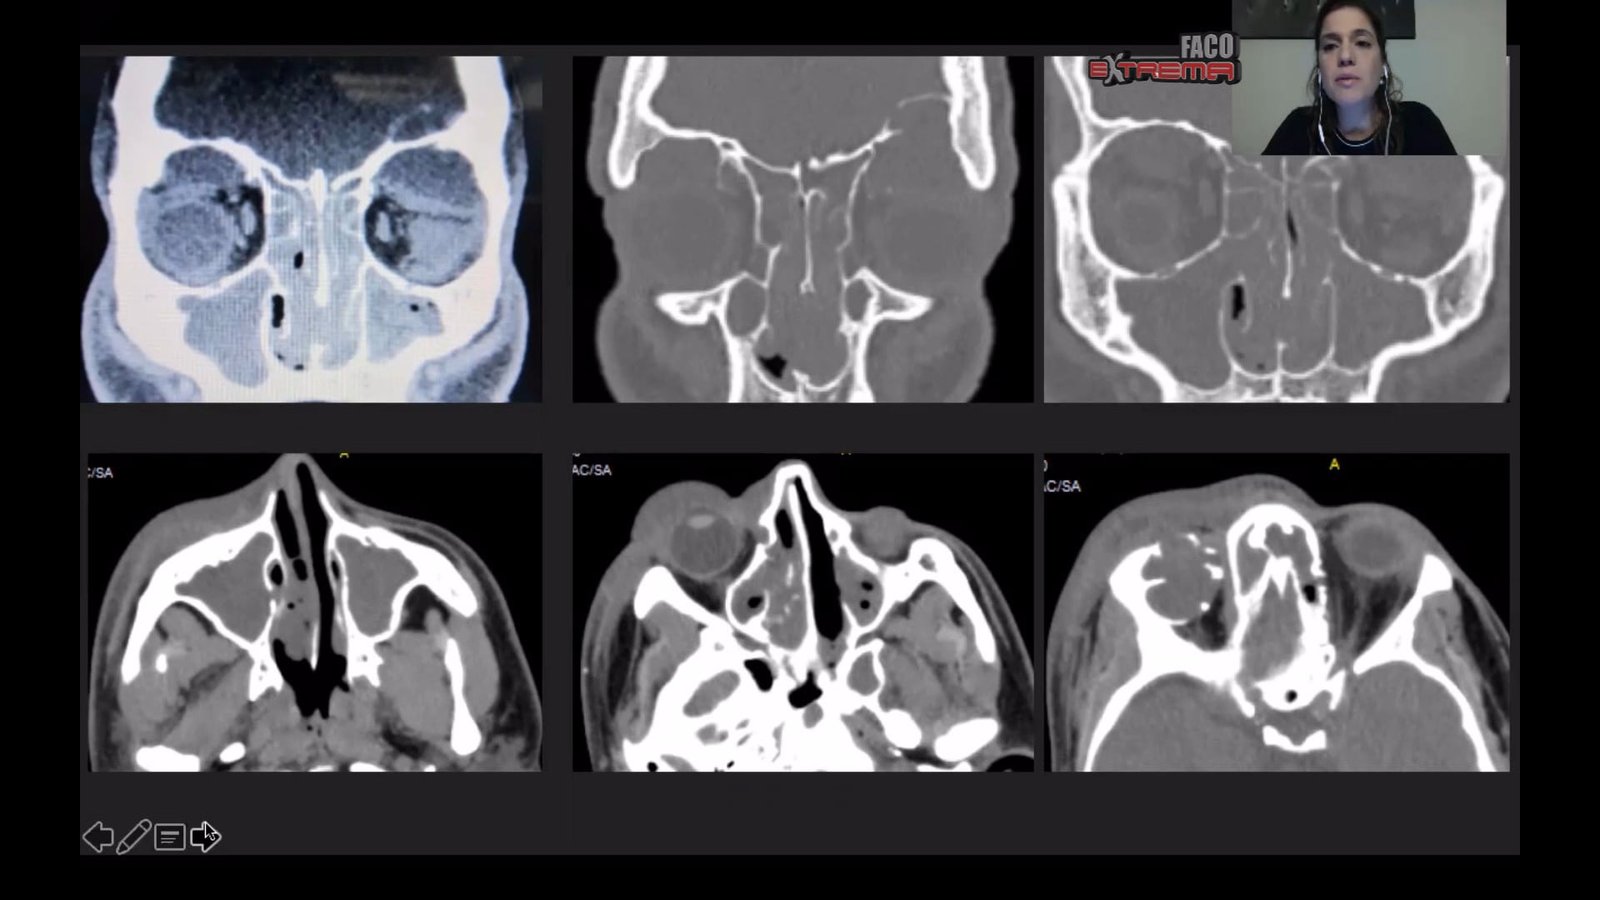

Trauma Extrema

Ximena Arze